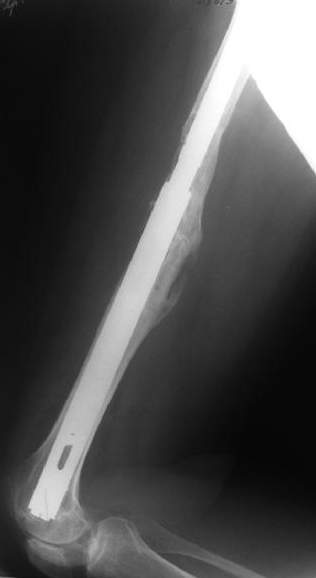

Female, rheumatoid, THA in 2003, car accident in 2006, failed plating. Nailing in Oct 2007. The nail is solid with hollow proximal part where the stem is docked. Last images are in 1 year after

nailing.

I have refreshed respect for the mighty femur and it’s incredible/remarkable ability to unite, regardless of what we do to it.

The femur responded by failure to Mennen plating (DePuy Bridge plate). So i would add that the ability to unite is realized in mechanically and biologically sound conditions.